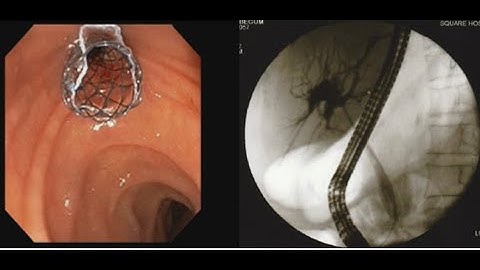

Cholangiocarcinoma ERCP Metallic Stent Deployment #BD_ENDOSCOPY